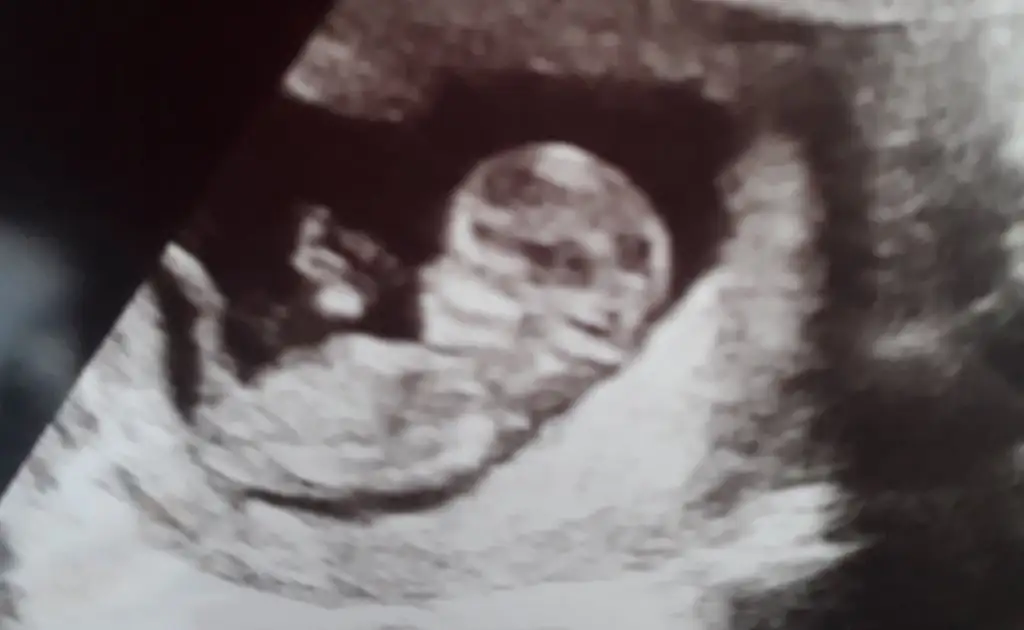

Merhaba arkadaşlar 11 haftalık ultrason görüntüsü, çookk merak ediyorum yorumlayabilir misiniz :))

Benımkı dogru cıkmadı malesef 2 defa erkem demıstınız 2 doktorda yuzde 90 kız dedı ama nub dık gıbıydı gercekten bende sasırdım